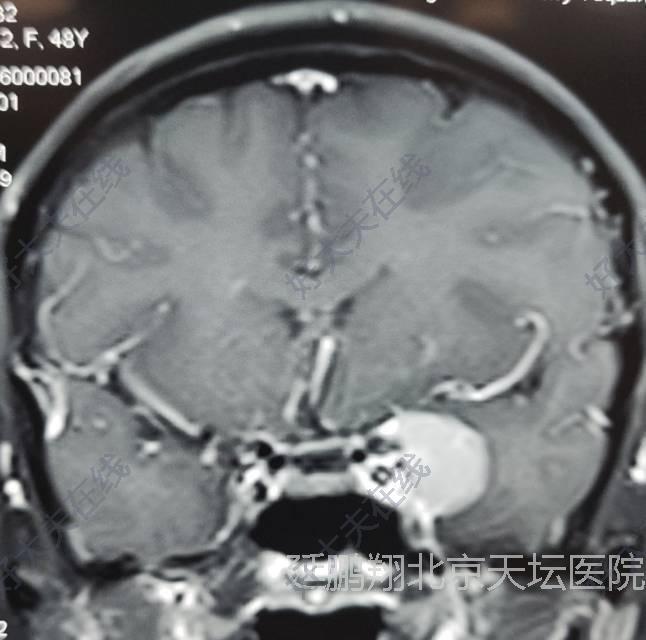

治疗前

女性,48岁。发作性心悸,心烦,头晕11月。CT和MRI显示左侧鞍旁脑膜瘤,与海棉窦及颈内动脉及大脑中动脉关系密切。